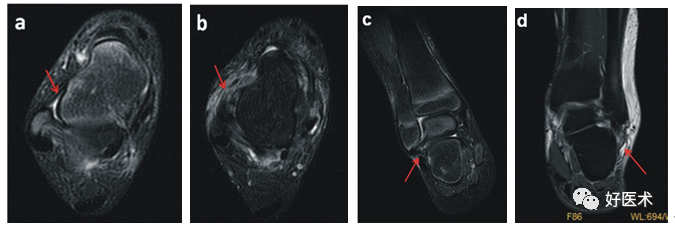

a.箭头所示为正常ATFL信号,形态规则,信号均匀,走形完整;b.箭头所示ATFL信号紊乱,未见形态完整的韧带组织;c.箭头所示为正常CFL信号,形态规则,信号均匀,走形完整,韧带存在良好的张力;d.箭头所示CFL信号紊乱,韧带迂曲松弛,韧带止点有高信号填充,疑似止点撕脱,外踝软组织肿胀明显(来自参考文献1)

慢性踝关节不稳的影像学检查

目前针对慢性踝关节不稳常用的影像学检查方式包括X线片检查、超声检查以及核磁共振检查等。

X线片检查可见不同程度骨赘形成,具有踝关节退行性变化。应力位X线片检查更具有临床诊断价值。

超声检查对于踝关节韧带损伤可以做出较为直接的诊断,并且可以进行动态观察,有时可能需要进行双侧对比检查。

目前MRI是诊断慢性踝关节不稳最好的方法,与X线片和超声检查相比,可以直观地显示受累韧带是否有水肿、增粗或连续性中断,可用于慢性踝关节不稳早期诊断,漏诊率低,临床应用广泛。所有影像学诊断的准确性受临床经验的影响。